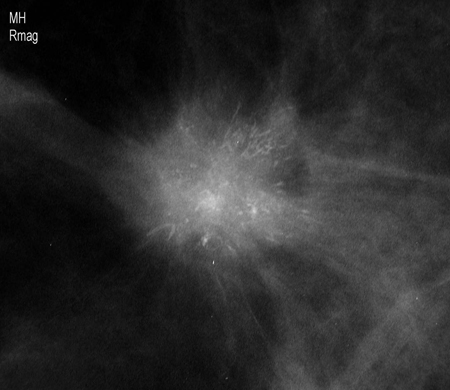

[Figure caption and citation for the preceding image starts]: Magnification view demonstrating irregular spiculated mass with associated calcificationsCourtesy of Dr Nancy Pile, University of Louisville; used with permission [Citation ends].